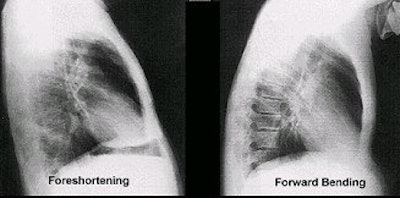

If the patient is leaning against the grid device (foreshortening) or forward bending, there is distortion of all thoracic structures. Image courtesy of Dr. Naveed Ahmad.AuntMinnie.com contributing writer